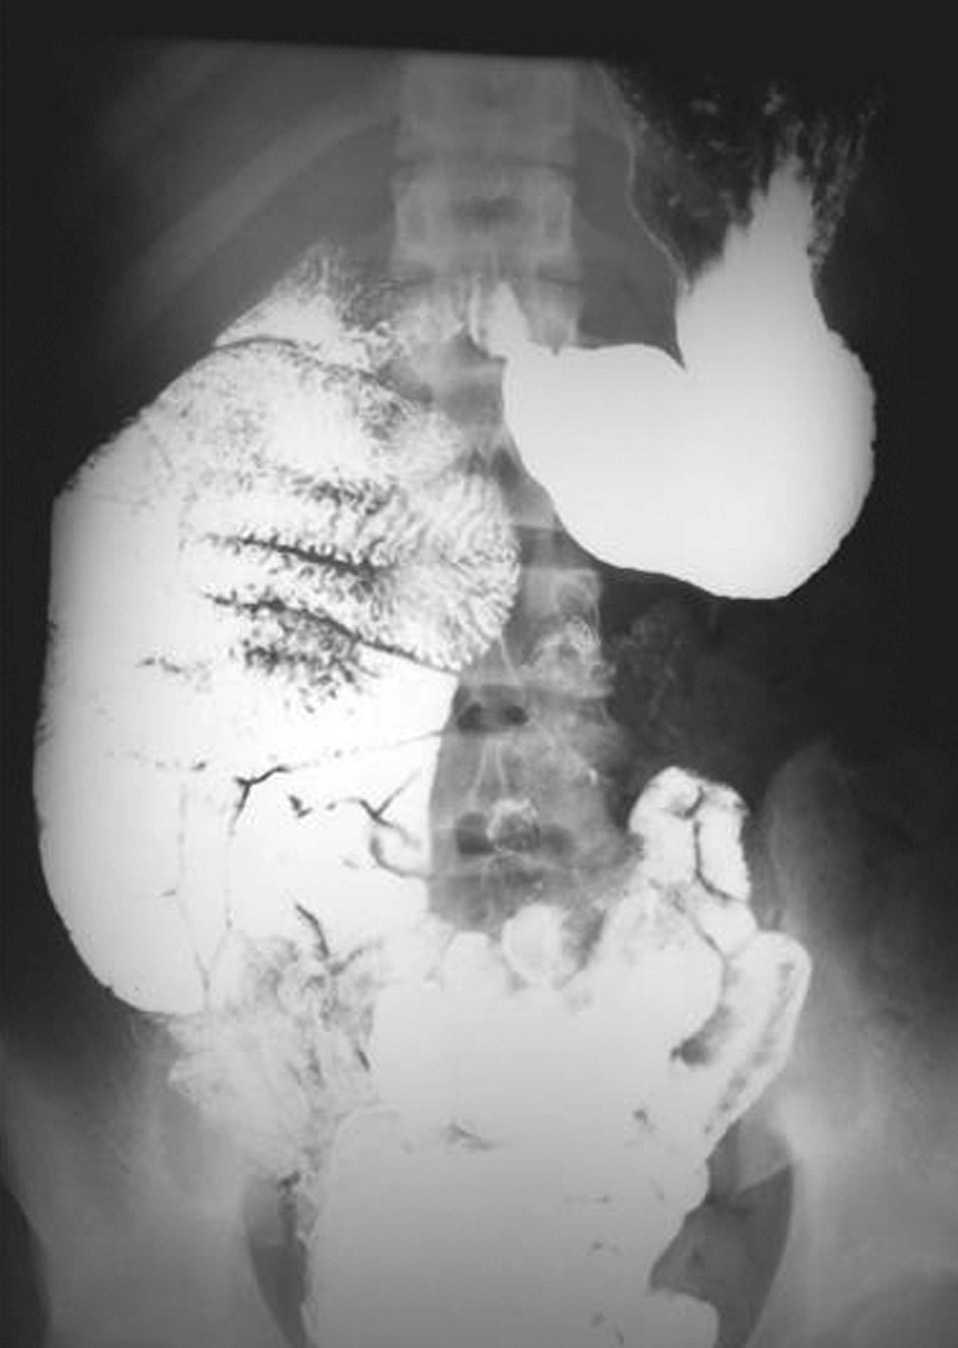

Fig. 1. Disposición derecha del paquete intestinal delgado y compresión duodenal (banda de Ladd).

Fig. 2. Disposición izquierda e inferior del colon.